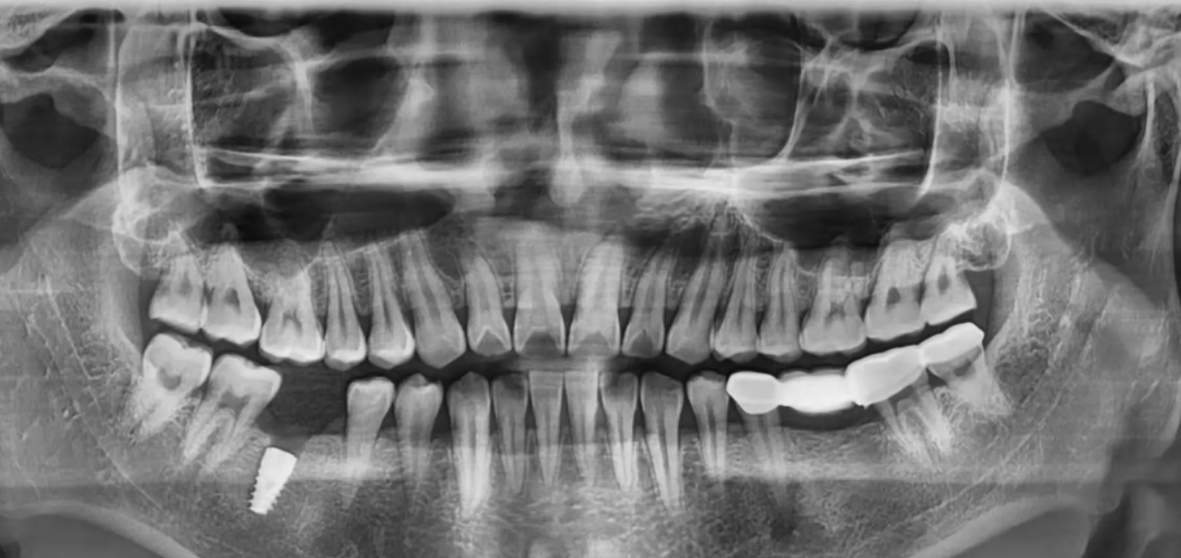

1、術(shù)前準(zhǔn)備,進(jìn)行種牙前,必要的X片、CT片以及抽血化驗(yàn)、量血壓等都是需要體檢檢查的。檢查完成后,醫(yī)生根據(jù)每個(gè)人的情況進(jìn)行個(gè)性化種植方案設(shè)計(jì)。